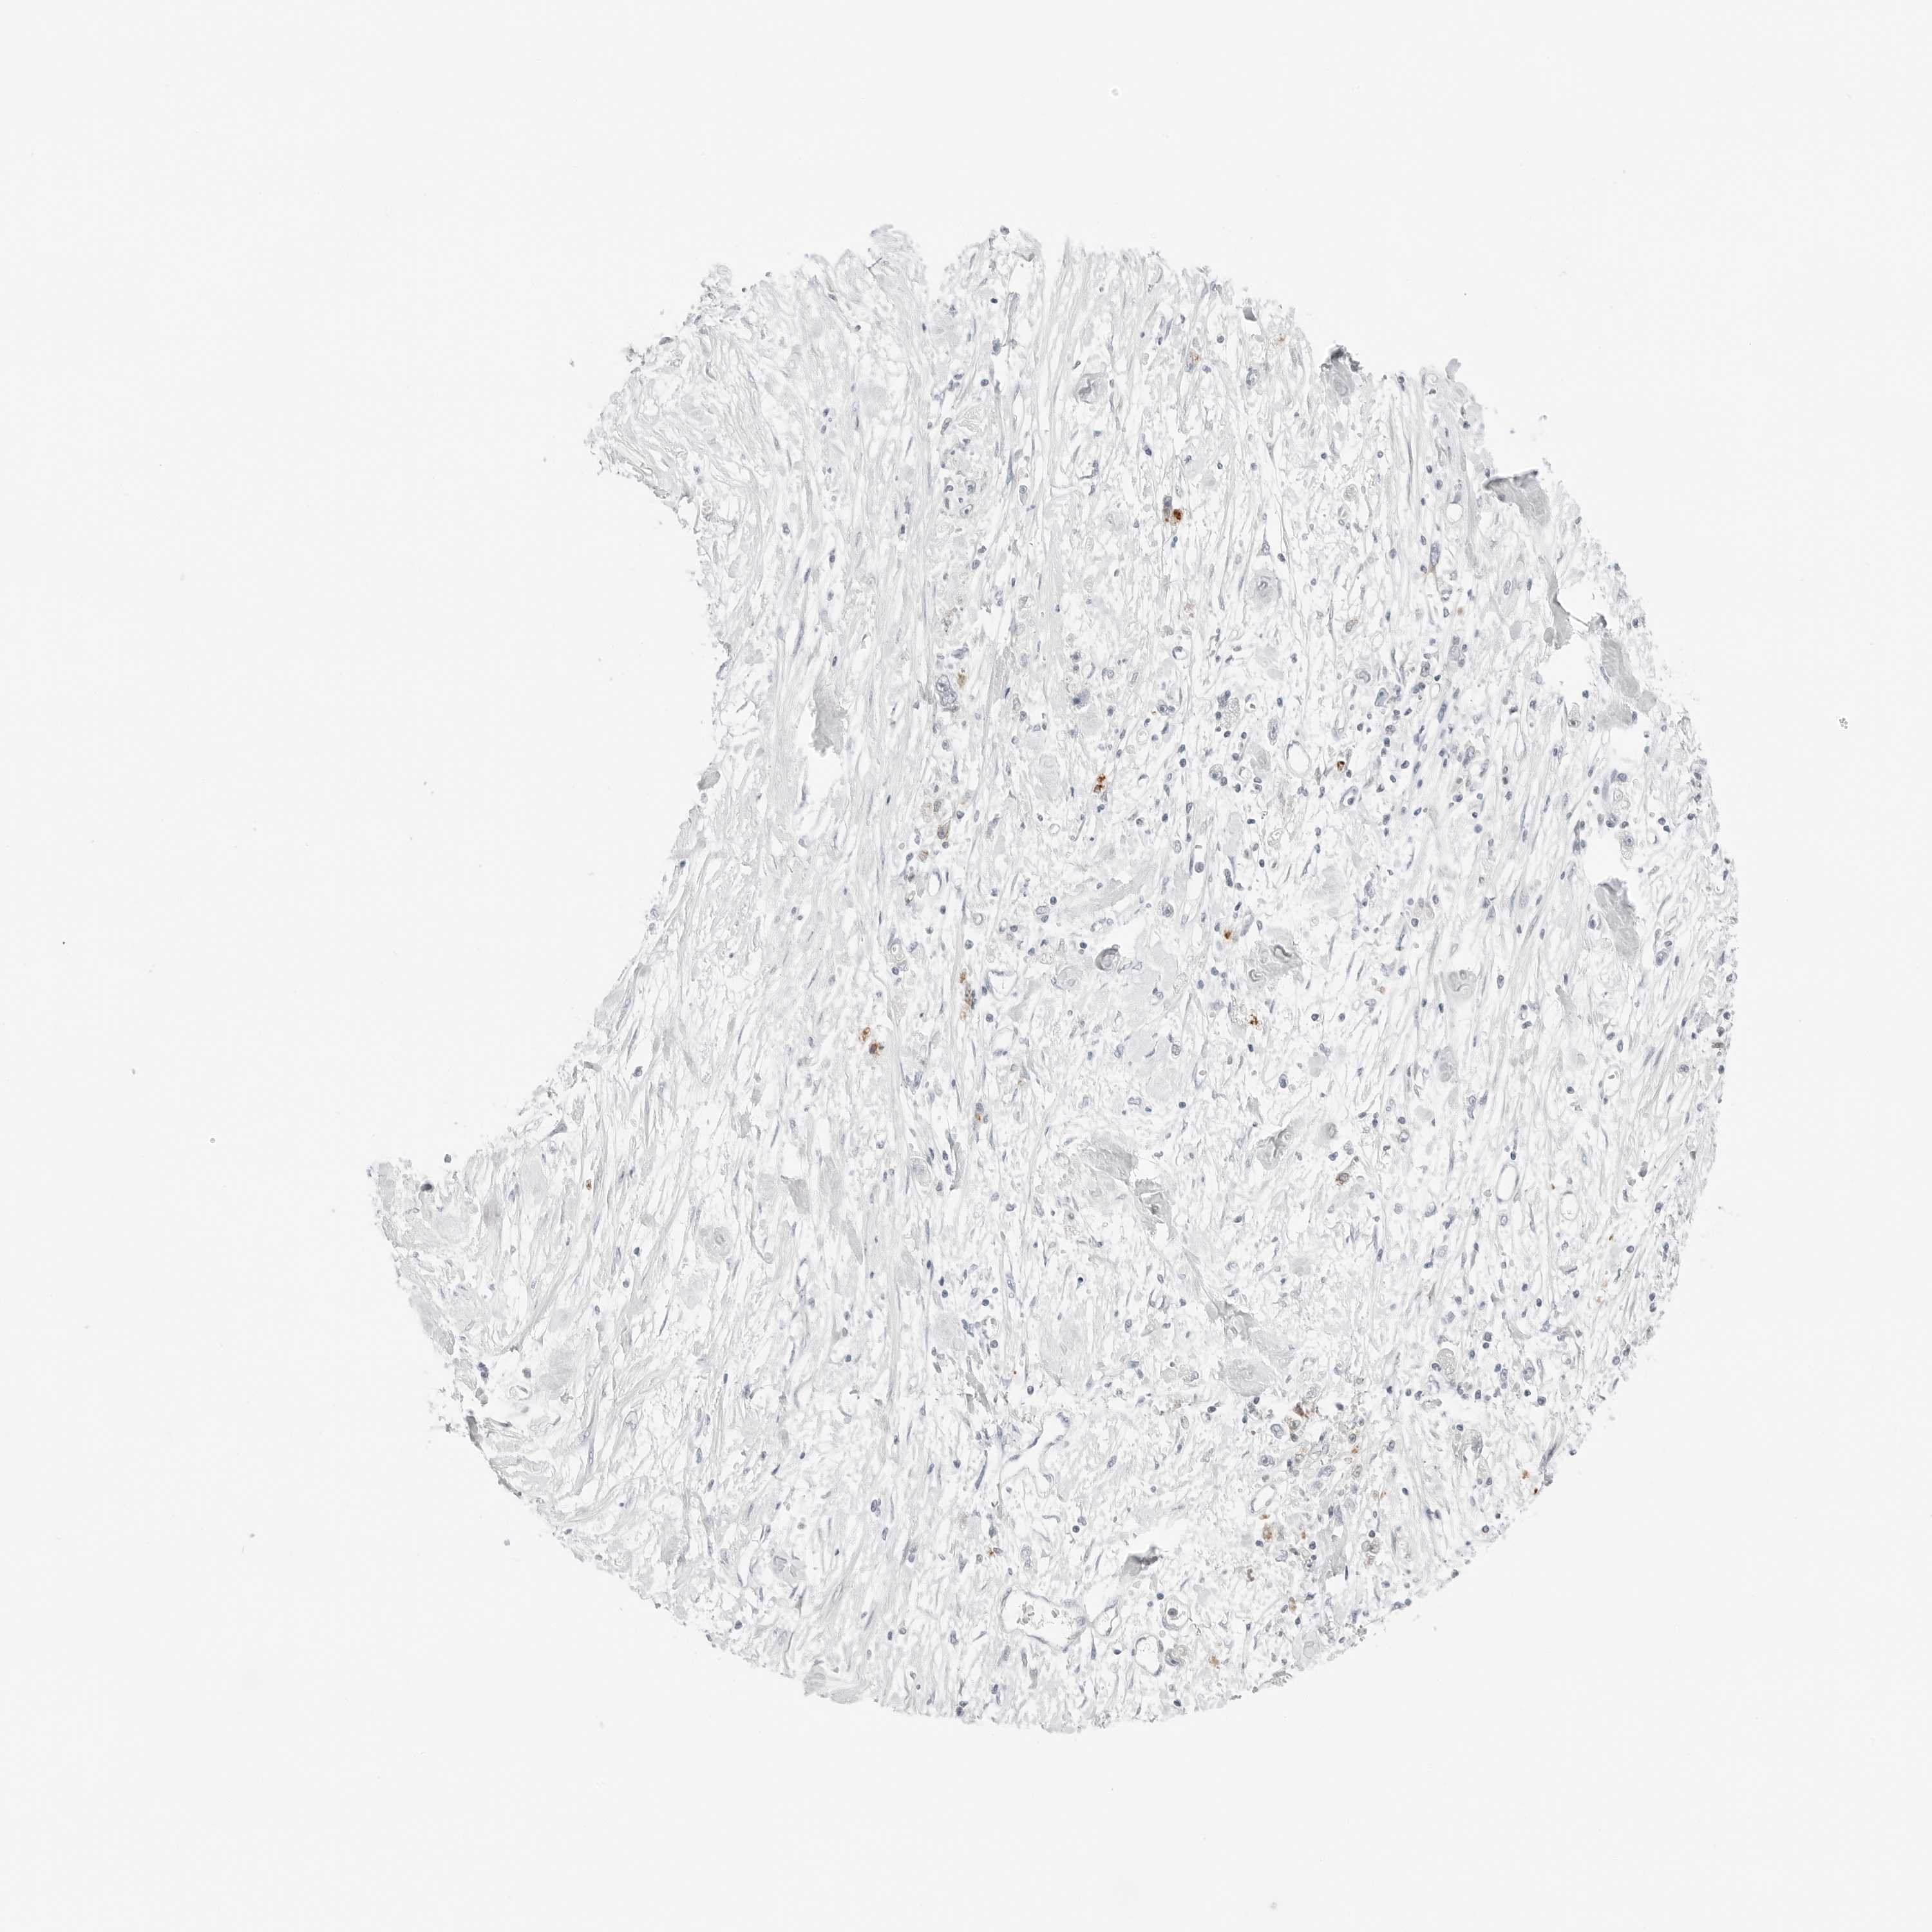

STOMACH CANCER - Protein expressioni

A mouse-over function shows sample information and annotation data. Click on an image to view it in a full screen mode. Samples can be filtered based on level of antibody staining by selecting one or several of the following categories: high, medium, low and not detected. The assay and annotation is described here.

Antibody stainingi

Antibody staining in the annotated cell types in the current human tissue is reported as not detected, low, medium, or high, based on conventional immunohistochemistry profiling in selected tissues. This score is based on the combination of the staining intensity and fraction of stained cells.

Each image is clickable and will lead to virtual microscopy that enables deeper exploration of all samples and also displays staining intensity scores, fraction scores and subcellular localization as well as patient and tissue information for each sample.

Antibody HPA028602

Antibody HPA028686

Staining

High

Medium

Low

Not detected

Adenocarcinoma, NOS